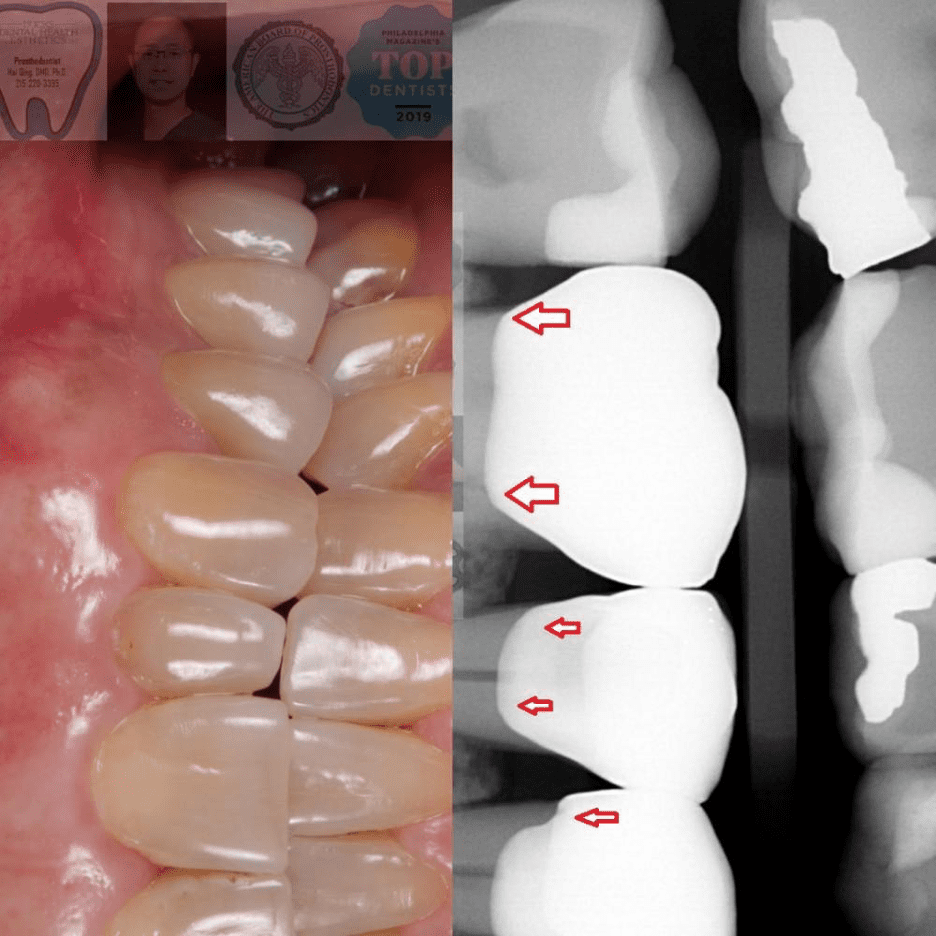

Dr. Qing is a Prosthodontist who is board-certified and specializes in crown restorations. What sets Dr. Qing's crowns apart is the attention to detail. The key elements for achieving long-lasting, comfortable, and aesthetically pleasing crowns lie in the finer points. These include the margin seal, which prevents any leakage after extended use,proximal contact that prevents food from getting stuck, occlusion that ensures a comfortable and functional bite, and color match, which provides a beautiful tooth and smile. By clicking the image at the bottom of the page, you can view the actual patients of Dr. Qing who have received crowns.

Click to See Dr. Qing’s actual patients who received crown treatment (The red arrows indicate the details of the crown margin seal, contour, and color match).